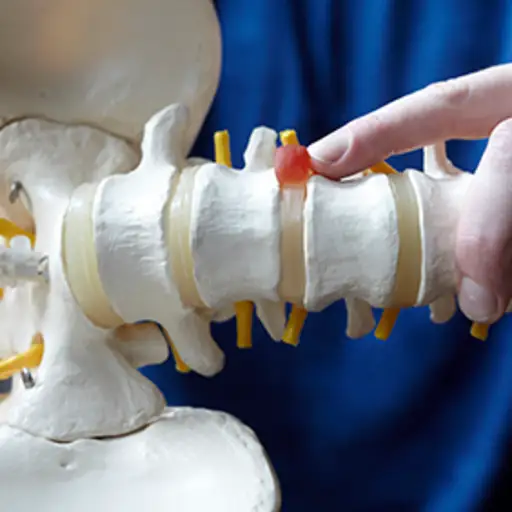

椎间盘突出

椎间盘突出,也称为椎间盘突出、滑移或破裂,是严重的背部疼痛和坐骨神经痛的常见原因。当椎间盘破裂或变薄,退变到椎间盘内的凝胶向外推入椎管时,腰椎区域的椎间盘就会突出美国神经外科医生协会。椎间盘突出压迫脊神经,常引起疼痛。

椎间盘变性

背部的椎间盘就像脊柱骨之间的减震器。作为一个正常的衰老过程,这些橡胶圆盘开始收缩,导致椎骨关节相互摩擦。并不是所有椎间盘退变的人都会背痛。然而,根据关节炎基金会对于退变椎间盘引起的疼痛不能归因于其他问题的人,他们被认为患有退变椎间盘疾病。

脊髓狭窄

椎管狭窄是指椎管狭窄或脊神经离开脊柱的开口狭窄。这种情况通常随着一个人的年龄增长和椎间盘开始萎缩而发展。与此同时,由于关节炎和慢性炎症,脊椎的骨骼和韧带肿胀或变大。椎管狭窄通常是由骨关节炎引起的美国风湿病学院。